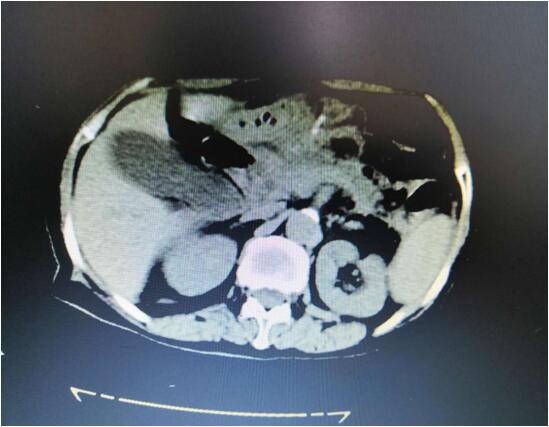

病例B

患者B,女,51歲,因牙齦出血1年入院,入院診斷為:乙肝,肝炎后肝硬化,門脈高壓癥,巨脾,脾亢,白細(xì)胞、血小板減少,中度貧血。5年前,曾在外院行介入脾栓塞術(shù),脾臟不僅沒有縮小,反而越來越大,脾下緣已經(jīng)超過腹部正中線、抵達(dá)臍部,就像幾個(gè)月“身孕”的婦女,給病人帶來巨大身心負(fù)擔(dān)。

(術(shù)前腹部CT顯示巨脾)

2020年2月28日,手術(shù)團(tuán)隊(duì)在3D腹腔鏡下為患者行巨脾切除術(shù)。因?yàn)椴∪嗽薪槿肫⑴K栓塞術(shù),手術(shù)遠(yuǎn)比想象中困難,巨脾與左側(cè)肝臟、膈頂、左側(cè)腹膜、結(jié)腸脾曲均有致密粘連,改變平時(shí)手術(shù)順序,先結(jié)扎脾動脈,離斷脾蒂,最后再分離脾周韌帶及粘連。完整切除巨脾后,分成小塊從小孔取出。